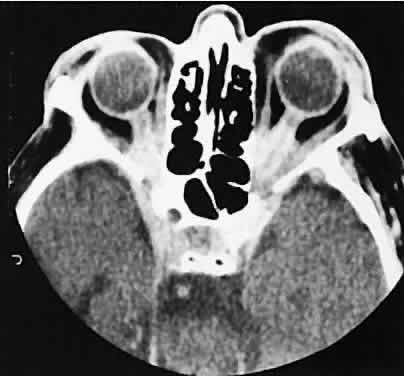

The edema and inflammatory infiltrate that accompany infections are indistinguishable from that associated with orbital inflammations. The presence of sinus disease, however, is a more constant feature with infections, because the sinus represents the infectious nidus in most cases (Fig. 9). In addition to the frequent appearance of sinus disease, the adjacent EOM is invariably enlarged. Less often, orbital infections may be transmitted through the blood, related to a retained foreign body, or spread from the lids. Chandler and colleagues47 classified orbital infections into five groups. Group 1 (preseptal cellulitis) represents inflammatory edema and reflects congestion of venous outflow. Group 2 has actual orbital infiltration/edema with mass effects and functional deficits. Group 3 includes patients with subperiosteal abscesses. Most of these dome-shaped subperiosteal abscesses are located along the medial wall. Group 4 includes patients with orbital abscesses who may display a ring-enhancing lesion with mass effect. Group 5 represents intracranial extension of the inflammation into the cavernous sinus or sinuses, which appear engorged and opacified.

Fig. 9. Orbital cellulitis. A. Axial view shows a subperiosteal soft-tissue mass displacing the medial rectus muscle. The ethmoidal sinus is opacified secondary to inflammatory disease, which invariably precedes the orbital inflammation. B. Coronal view further shows the subperiosteal and ethmoidal sinus inflammation. Inflammation changes also are seen in each maxillary sinus.